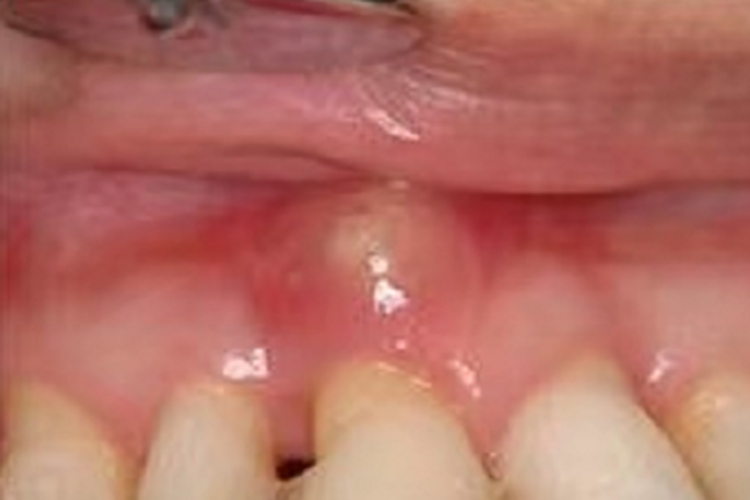

根尖周炎发生后,可见患处有脓包,大小不定,表面光滑。本病常继发于龋齿、牙髓炎等情况,应遵医嘱进行治疗。

根尖周炎导致的损害可表现为脓包,呈半球形,无明显疼痛感,表面光滑,有弹性,大小不定。患者在咀嚼食物时,可觉局部有异物感,建议及时就医。

对于根尖周炎的治疗,应尽可能消除炎症,尽量保存患牙,恢复患者的咀嚼功能。对于局部形成脓肿、脓疱等情况,需要进行切开引流处理。对于患牙需进行根管治疗,并用消毒剂进行冲洗,可搭配抗生素等药物缓解炎症。对于无法保留的患牙,可视情况进行拔除。注意上述治疗均需遵医嘱治疗。